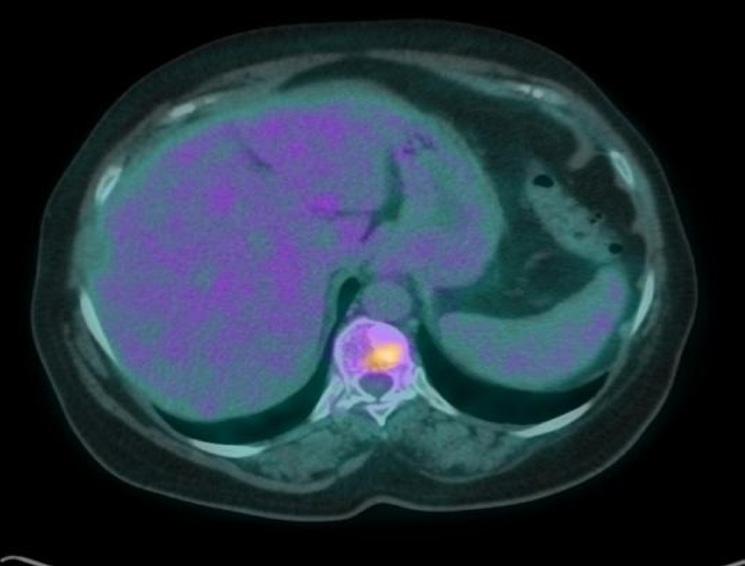

La PET (figura 1) metteva in evidenza la presenza di accumulo del tracciante metabolico in corrispondenza della formazione ovalare posta nel quadrante inferoesterno della mammella di sinistra (SUV massimo pari a 5,6). In in sede ascellare monolaterale, ulteriore grossolano linfonodo caratterizzato da analoga attività metabolica (SUV massimo pari a 5,1). Si segnalano inoltre, la presenza di alcune focalità di accumulo del tracciante metabolico di pertinenza scheletrica poste nel soma di D2, D11 e nell’emisacro di sinistra.

1. PET Ottobre 2018.